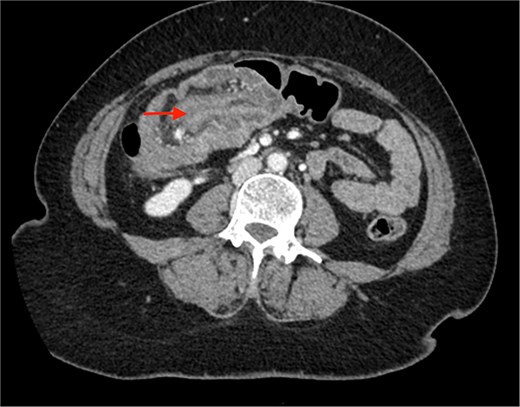

A CECT scan of the abdomen and pelvis revealed circumferential heterogeneously enhancing mucosal wall thickening involving caecum and ascending colon with pericolic fat stranding and ileocolic intussusception along with multiple enlarged heterogeneously enhancing necrotic lymph nodes in right iliac fossa and pericolic region (Figs 1 and 2).

Contrast enhanced CT of the abdomen showing bull’s eye sign (arrow) suggestive of ileocolic intussusception.